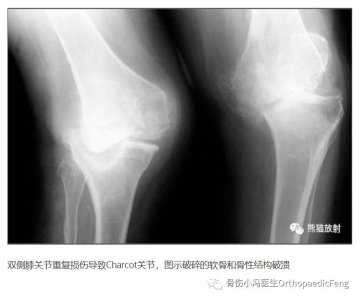

- 「科普」不痛的罕见关节病---夏科氏关节